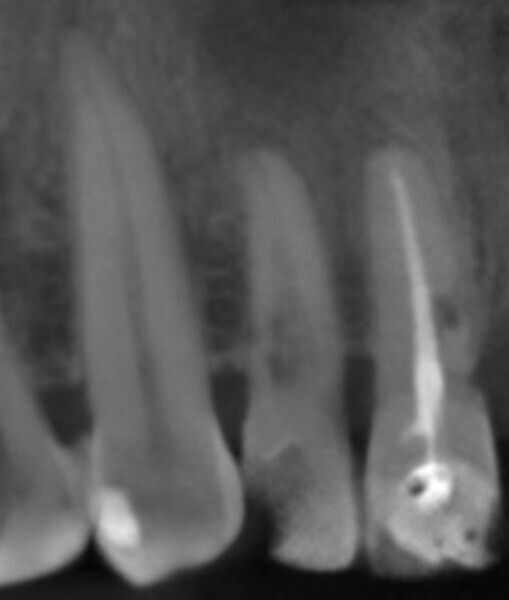

Immediate placement and restoration of a Straumann BLX implant replacing maxillary incisors